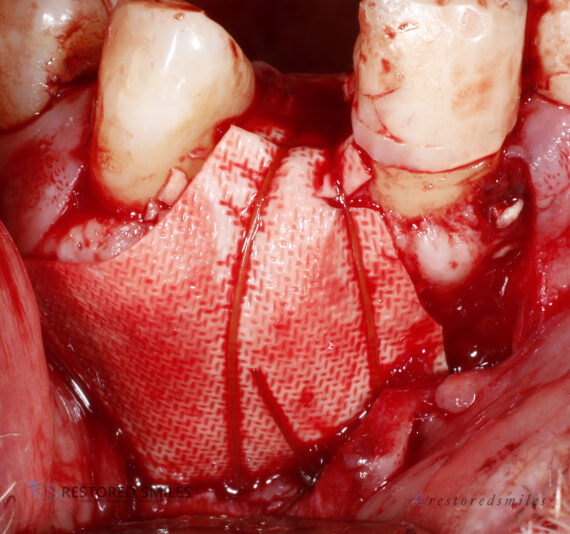

• This case was a tricky one. Sometimes, we just need to do the best with what our patients anatomy gives us. Patient was referred to me wanting an implant and there wasn’t much to work with and oh yeah, the mental foremen was smack dab in the middle of our sight.

With the help of some buccal plate decorticating, a tenting screw, and some CGF/PRF…

• This was a tough case with a large through-and-through defect on an upper central incisor. After the area was throughly cleansed I grafted using mineralized cortical particulate with CGF/PRF protocols. A thick collegen resorbable membrane was secured with membrane stabilizing sutures and primary closure achieved with a nonresorbable PTFE…

Read more